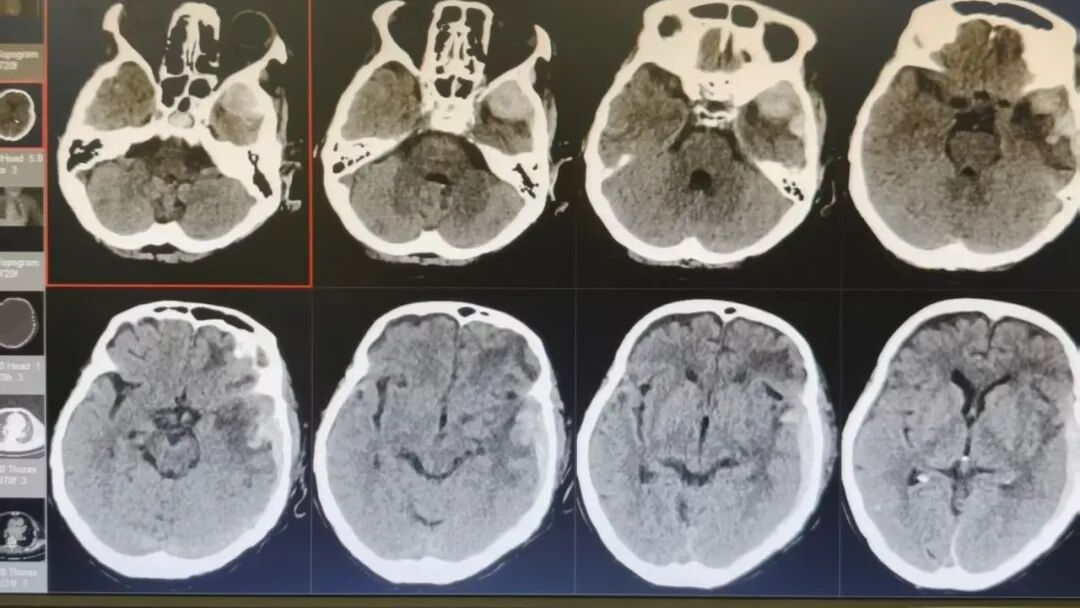

89 岁的吴阿婆(化名)突发意外,被发现时已意识不清、陷入昏迷。家人发现后,紧急将其送往漳州第三医院,检查结果令人揪心:重型颅脑损伤、脑内大面积出血,加之 O 型 Rh(D) 阴性熊猫血、严重贫血······多重致命高危因素叠加,病情十分危重。

如此复杂凶险的状况,在常人看来几乎已是绝境!但漳州第三医院神经外科团队没有放弃,考虑到阿婆身体条件极差、血型特殊、手术风险难以预估,最终摒弃常规开颅方案,为她量身制定了个体化精准保守治疗方案,在绝境中为生命守住一线希望。